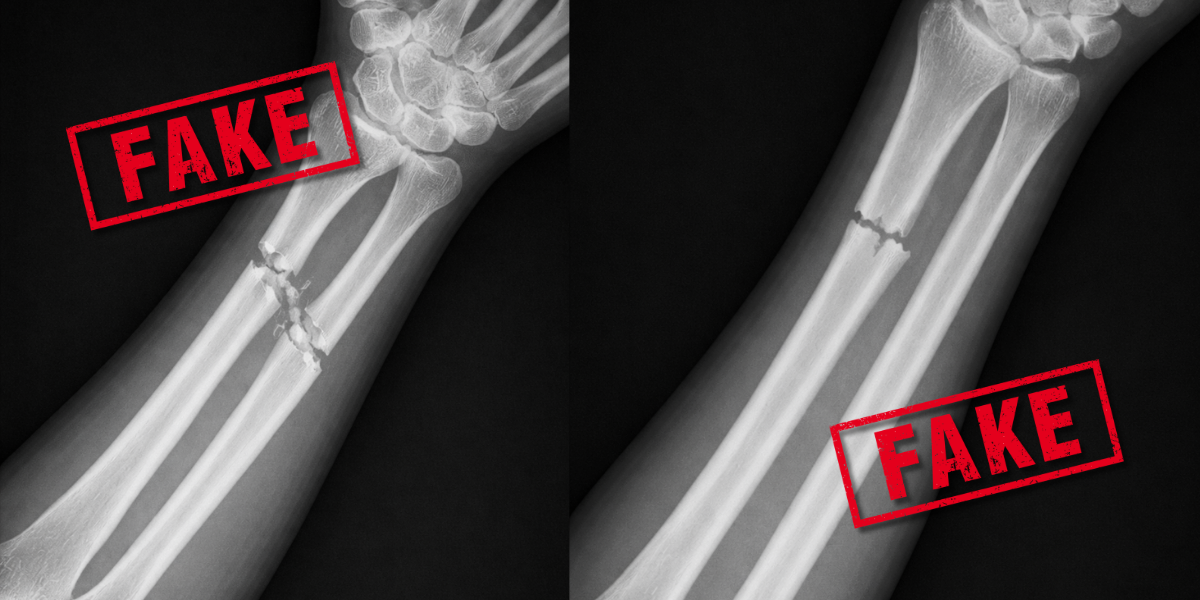

Manipulierte Röntgenbilder sind medizinische Aufnahmen, die mithilfe von Künstlicher Intelligenz oder Bildbearbeitung gezielt verändert oder vollständig neu erzeugt werden. Ziel ist es meist, Krankheiten vorzutäuschen oder zu verschleiern, um finanzielle Vorteile zu erlangen. Durch den rasanten Fortschritt der KI lassen sich heute Bilder erzeugen oder verändern, die von Originalaufnahmen kaum zu unterscheiden sind. Was als „Deepfake“ in sozialen Netzwerken begann, hat längst kritische Bereiche erreicht. Versicherungen stehen deshalb vor einer neuen Dimension des Abrechnungsbetrugs.

Typische Merkmale von Deepfake Röntgenbildern sind übermäßig glatte Knochen und unnatürlich gerade Wirbelsäulen. Dennoch: die Qualität der künstlichen Bilder nimmt stetig zu, unabhängig von der Körperregion, was die Erkennung erschwert. Die nicht erkennbaren Deepfake-Röntgenbilder gefährden die Diagnosesicherheit, untergraben das Vertrauen in digitale Patientenakten und werden für perfiden Versicherungsbetrug genutzt.

Teilweise ja – etwa unnatürlich glatte Strukturen oder anatomische Unstimmigkeiten. Allerdings werden diese Merkmale durch immer bessere KI-Modelle zunehmend reduziert, sodass sie oft nicht mehr sichtbar sind.